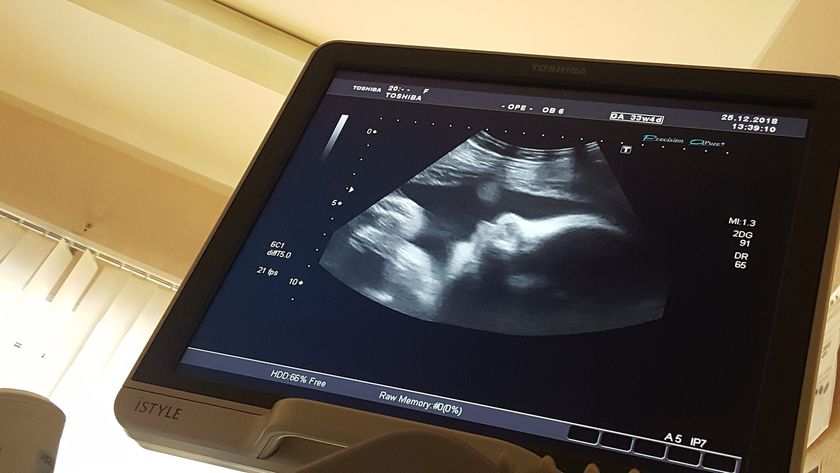

Была на повторном узи, но не было времени написать!) Все у нас хорошо, малышка в головном предлежании ?? весит уже 2059 грамм, врач сказала это абсолютно нормальный вес. Все развивается согласно сроку!) Допплер сосудов хороший. Степень зрелости плаценты 1, я не знаю хорошо это или нет) но написано, что соответствует сроку беременности. Вод нормальное количество) Шейка до 37 см) Ну вот как-то так) завтра пойдём с утра на ктг ? Как у вас дела?) Какой вес был у ваших малышей на 32-33 неделе?